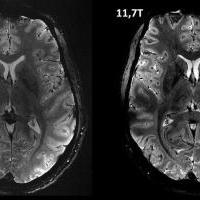

twitter.com twitter.com

Cerveau: comparaison d'une vue zoomée du lobe occipital à 7T et à 11,7 T, à même résolution et à temps d'acquisition identique

@CEA_Officiel 2 ans